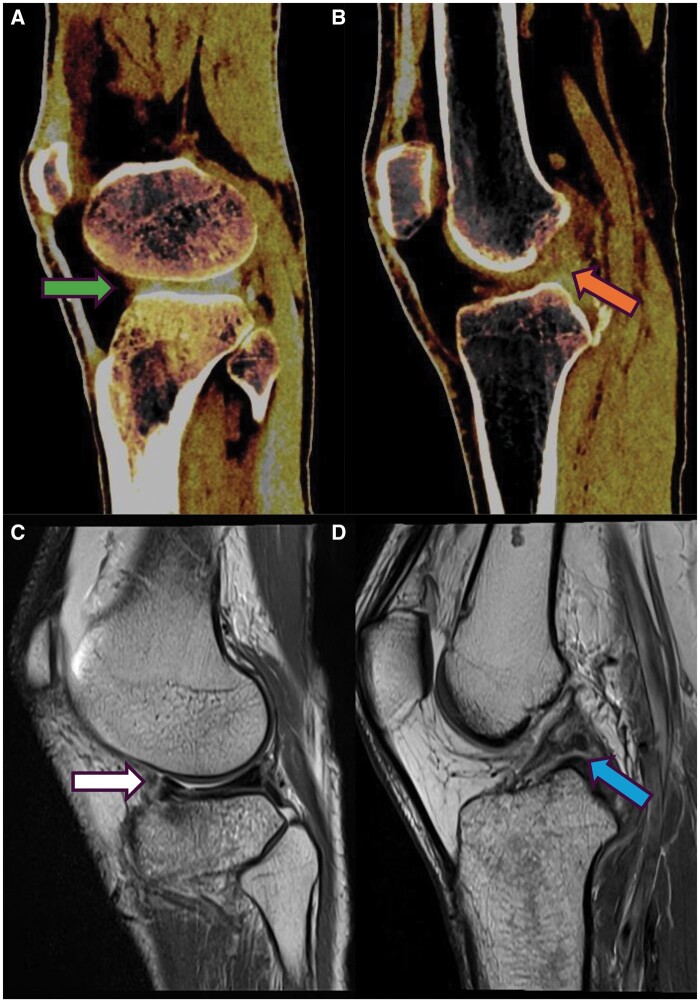

Dual-energy computed tomography (DECT) is an advanced imaging technique that acquires data using two distinct X-ray energy spectra, typically at 80 and 140 kVp, to differentiate materials based on their atomic number and electron density. This capability allows for the enhanced visualisation of various pathologies, including bone marrow oedema (BMO), by providing high-resolution images with notable energy spectral separation while maintaining radiation doses comparable to conventional CT. DECT's ability to create colour-coded virtual non-calcium (VNCa) images has proven particularly valuable in detecting traumatic bone marrow lesions (BMLs) and subtle fractures, offering a reliable alternative or complement to MRI. DECT has emerged as a significant tool in the detection and characterisation of bone marrow pathologies, especially in traumatic injuries. Its ability to generate high-resolution images and distinguish between different tissue types makes it a valuable asset in clinical diagnostics. With its comparable diagnostic accuracy to MRI and the added advantage of reduced examination time and increased availability, DECT represents a promising advancement in the imaging of BMO and related conditions.